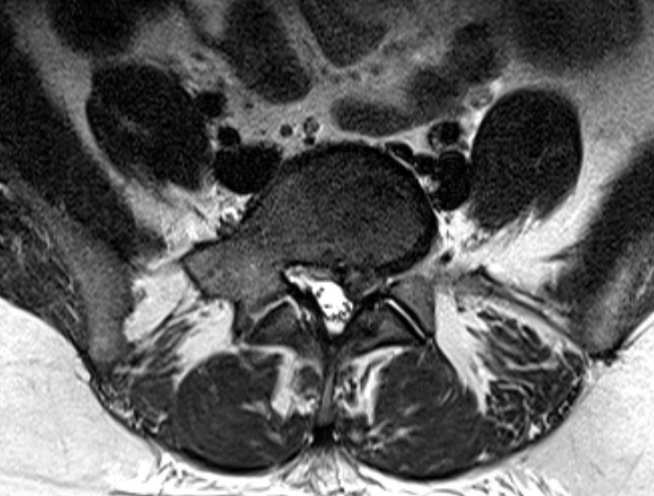

The outcome of spinal decompression surgery is highly variable with recently published data suggesting ~56% of patients improve and ~44% show no improvement or worsening of the condition. The surgical decision is currently made following static MRI of the lumbar spine, which provides information about abnormalities of relevant structures (e.g. intervertebral discs). However, this does not permit any inferences about the structural integrity or damage to nerves leaving the spine which ultimately defines the symptoms. This ongoing project funded by the Wellcome Trust and Imperial College aims to develop diffusion tensor imaging protocols to allow identification and tracking of compressed lumbar nerves in patients with sciatica due to herniated intervertebral disc waiting to undergo surgery. Additionally, the relationship between the imaging data and the functional integrity of motor pathways will be assessed neurophysiologically with transcranial magnetic stimulation. Image analysis techniques will also be developed to automate the localization and quantification of abnormalities from lumbar MRI scans. Machine learning techniques will be employed to identify groups and determine which parameters (e.g. imaging, neurophysiological, structural parameters, clinical scores) can effectively separate the groups. This computational approach will also be applied to generate models to attempt to predict the outcome of spinal surgery; comparison of pre- and post-surgical imaging data will aid with generating these predictive models.